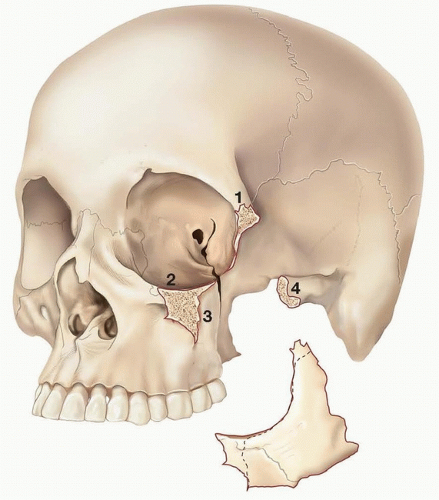

Le Fort fracture

Le Fort I dentoalveolar separation including pterygoid plates

Le Fort II bilateral pyramidal fracture including pterygoid plates

Le Fort III craniofacial separation involving the frontonasal articulation, traversing the orbital walls with disjunction of pterygoid plates and zygomatic arch (FIG 1)

The zygomaticosphenoid junction is the key anatomical articulation in the reduction of these fractures (FIG 2).